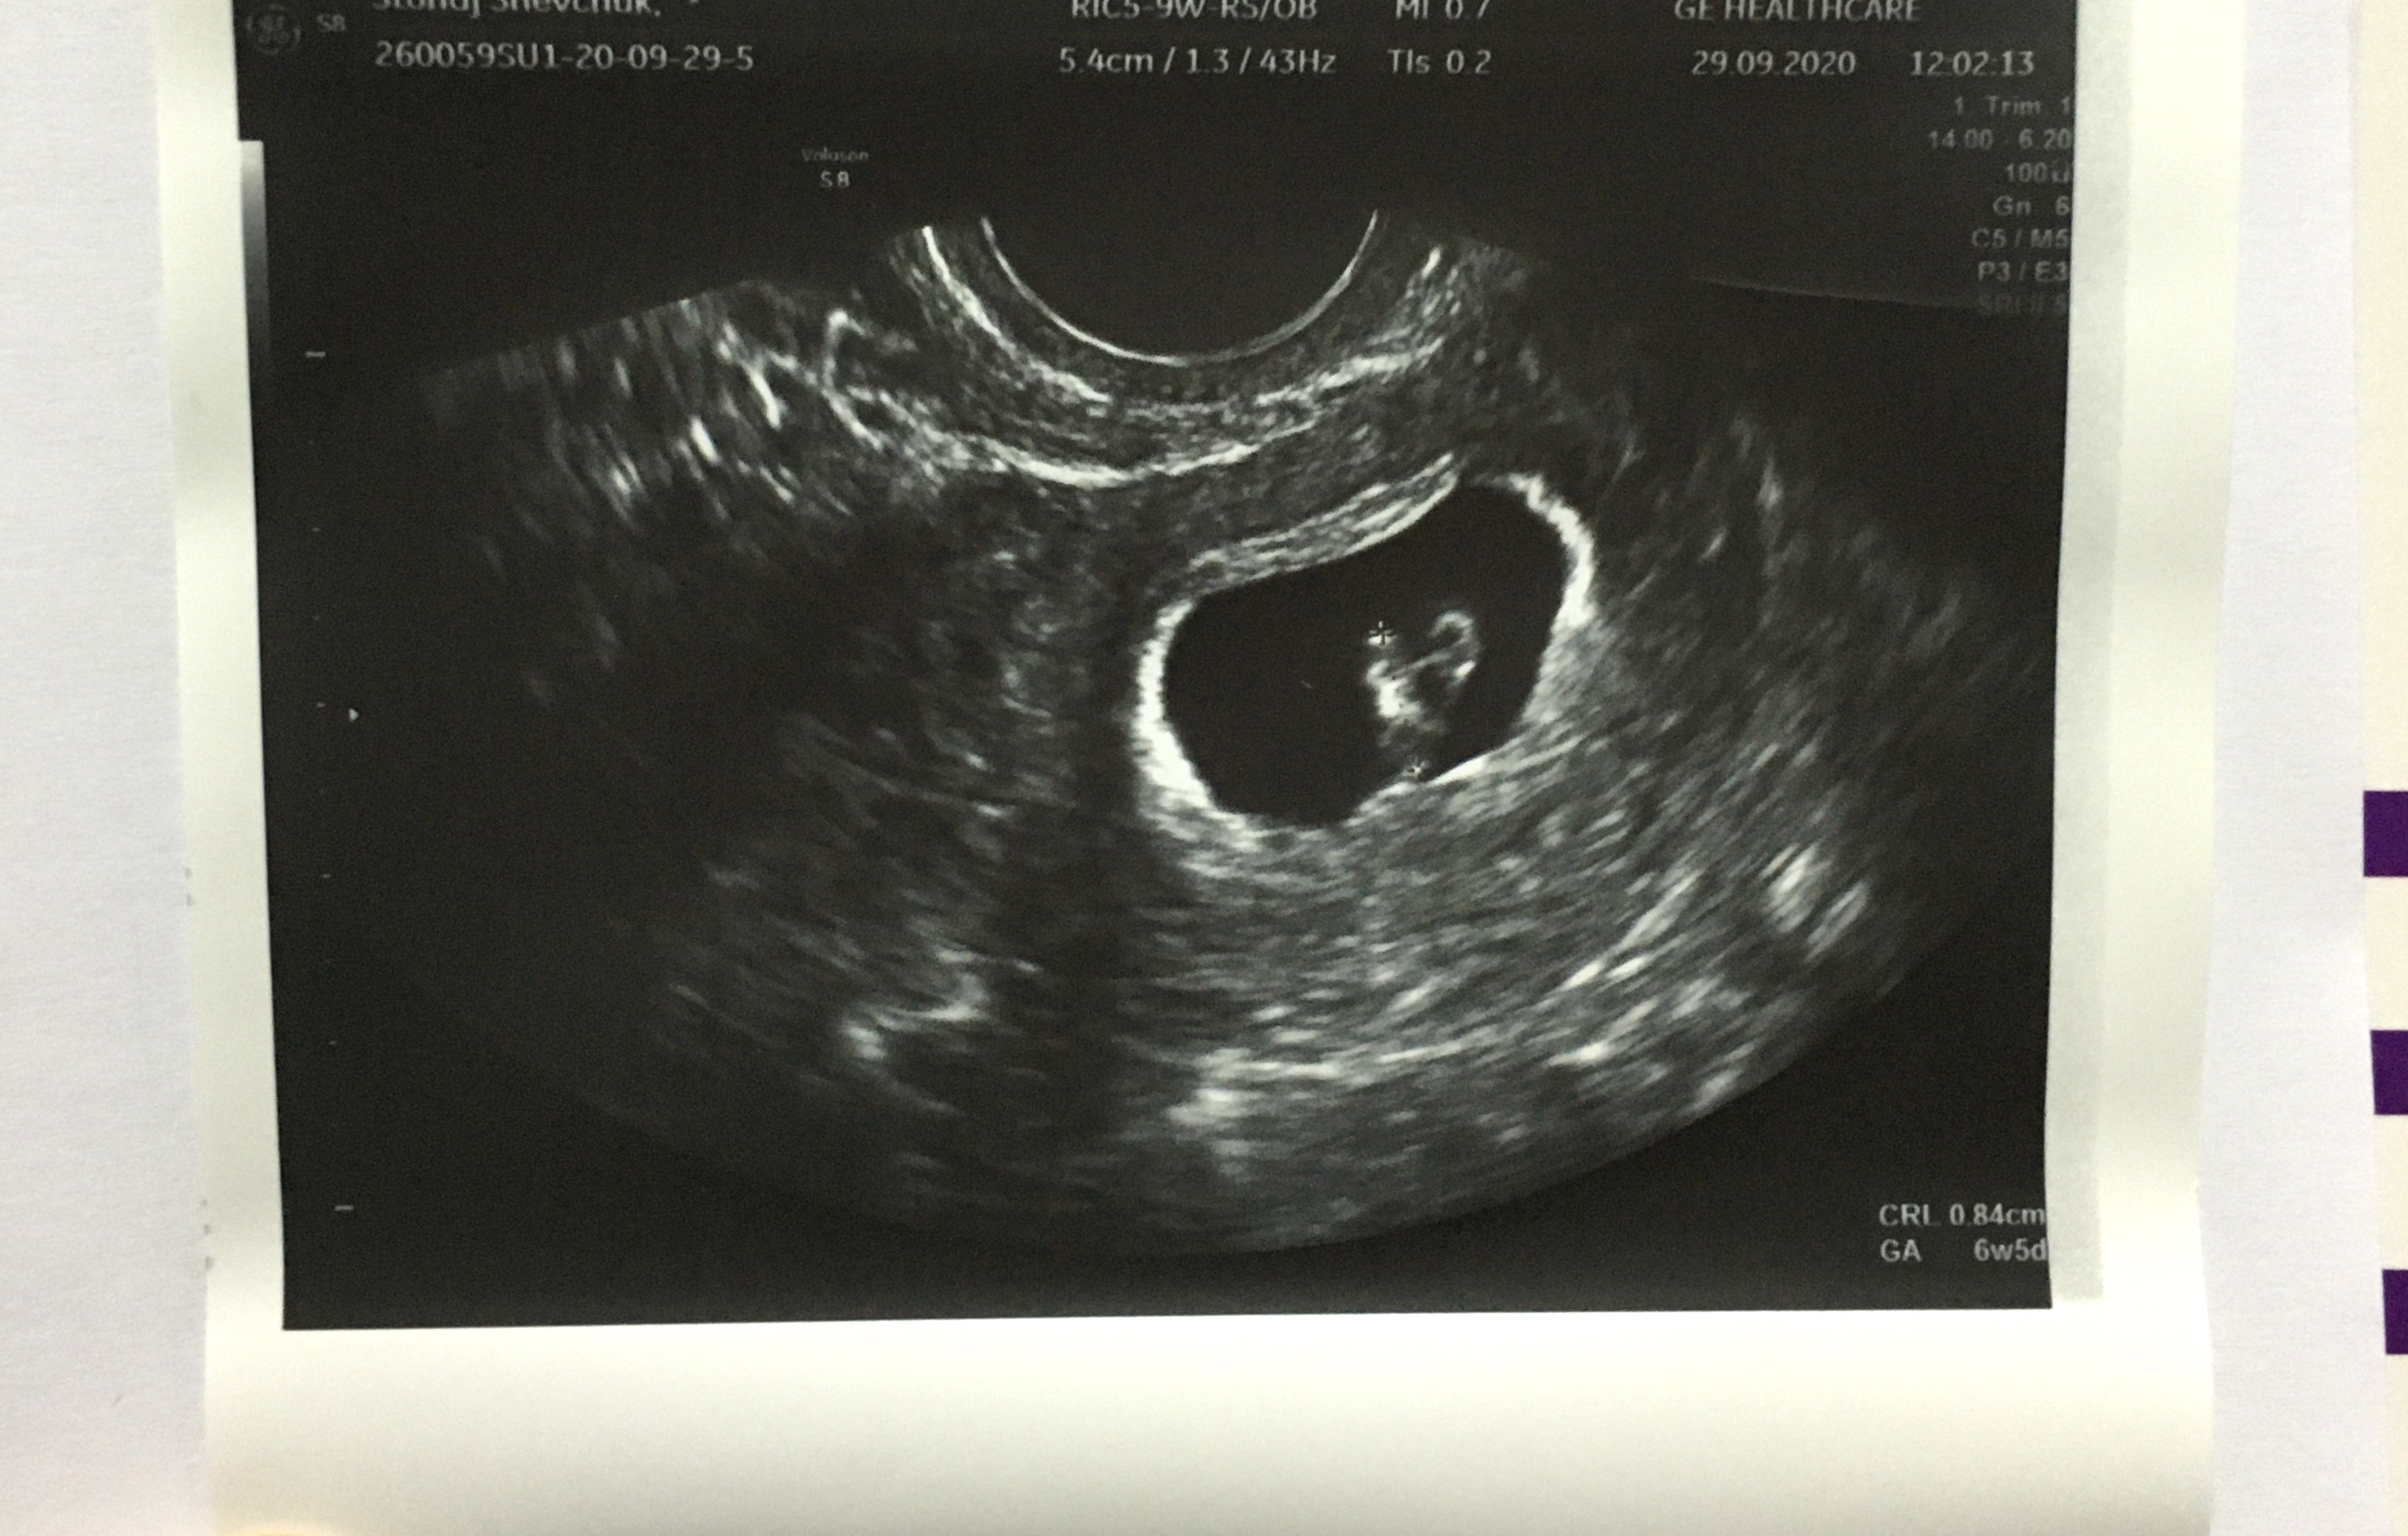

Cześć dziewczyny! My tez byliśmy dzisiaj ja wizycie. Mamy 6+4, wg usg wychodzi 6+5. Serce dobrze widoczne